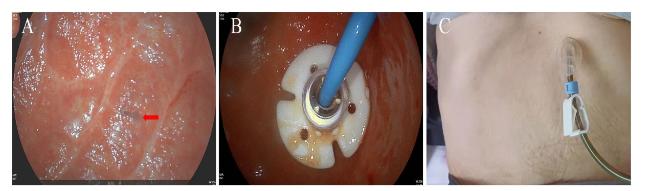

患者入院后于2021年8月24日行胃镜检查提示食管入口、食管中下段距门齿约30~40 cm处明显狭窄(图1A),予探条扩张后方能入镜至胃内,见胃窦变形,小弯侧大片溃疡形成,底覆白苔,周边黏膜充血水肿,幽门结构难以辨认(图1B),予球囊扩张(图1C),并放置鼻空肠管,术后第二天予肠内营养,但患者出现恶心、呕吐以及腹胀症状。2021年8月25日行上消化道碘剂造影显示食管上段、中下段狭窄,造影剂通过欠顺畅(图2);部分胃体、胃窦僵硬、狭窄并梗阻。心理科会诊提示患者有消极轻生念头,考虑为抑郁焦虑状态。经上述治疗后,患者肠内营养耐受情况欠佳,病情未见明显改善,梗阻仍然存在。经医务人员综合评估,确认该患者具有行PEG/J的适应证,无禁忌证。获得患方知情同意后,于2021年8月28日在气管插管全身麻醉下行PEG/J。患者取仰卧位,麻醉后经口插入胃镜,见食管仍狭窄,入镜至胃内,见胃腔变形,胃底较多胃液潴留,吸净后继续入镜至胃窦、幽门前区,见幽门仍狭窄,仔细辨认后送镜至十二指肠,见球部、降段黏膜光滑,退镜至胃体部,注气后于左上腹反复运用传统指压试验及透光试验寻找理想穿刺点,由于胃腔变形、胃移位,术者反复多次选点失败,后联合运用负压针吸试验,用含5 mL 生理盐水的注射器抽吸针筒保持负压,同时保证胃腔内充分注气,再次选定穿刺点后经腹部皮肤逐层缓慢穿刺至胃腔(图3A),最终定位于剑突下2 cm偏左约3 cm,消毒铺巾后,采用牵拉法完成胃造瘘术,并经胃造瘘管(管径6 mm)送入小肠管(管径3 mm)至空肠上段(图3B[5]。患者术中、术后生命体征平稳。于术后6 h开始向小肠管内注入少量营养液并逐量增加至正常管饲量,后逐渐过渡至日常食糜。经处理,患者病情及营养状况逐渐好转,于2021年9月25日出院。1个月后患者遵嘱返院复诊,监测体质量由住院期间最轻时39 kg增至47 kg,复查碘剂造影示食管上段狭窄较前减轻,中下段食管狭窄;胃窦部至幽门区明显狭窄伴梗阻,仅见少许造影剂通过幽门。医师与患方保持电话随访至撰稿日,得知患者呕吐次数逐渐减少至缓解,营养状况持续改善,造瘘管固定良好,造瘘口无红肿、渗液等(图3C)。

图1 一例上消化道严重腐蚀患者的胃镜图片

注:A 为食管入口;B 为胃窦及幽门处;C为 球囊扩张幽门入口。